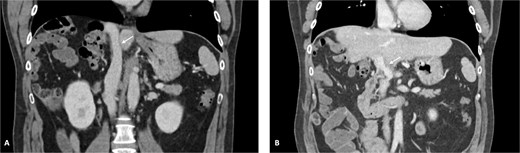

Vascular clamps were applied to the IVC. Before resection, we measured the expected vascular defect. An IVC defect measuring 5 cm in length and 2.5 to 3 cm in width was confirmed. The patch was tailored to 6 × 4 cm, allowing a repair larger than the defect to avoid tension and stenosis. We proceeded with resection of the IVC anterolateral wall. Reconstruction using the APFP, with the mesothelial side of the patch facing the lumen, was performed using a running 4–0 polypropylene suture (Fig. 4). It is essential to flush the vein with heparinized saline and avoid suture tension. Total IVC clamping time was 30 min. The video vignette demonstrates the surgical technique. The specimen is shown in Fig. 5.

Final specimen. The resected specimen shows intrahepatic cholangiocarcinoma with invasion of the IVC.

The post-operative period was complicated by bleeding from the left epigastric artery at the APFP harvesting site on post-operative day 14, requiring reintervention and vessel ligation. The patient was discharged on post-operative day 31. Pathology confirmed an ypT4G2N1R0 small-duct intrahepatic cholangiocarcinoma. No post-operative thrombosis or clinically significant stenosis were identified. Figure 6 demonstrates the reconstructed vessels 1 year after surgery. After completing 6 weeks of therapeutic low-molecular-weight heparin (LMWH), the patient continued rivaroxaban 20 mg once daily.